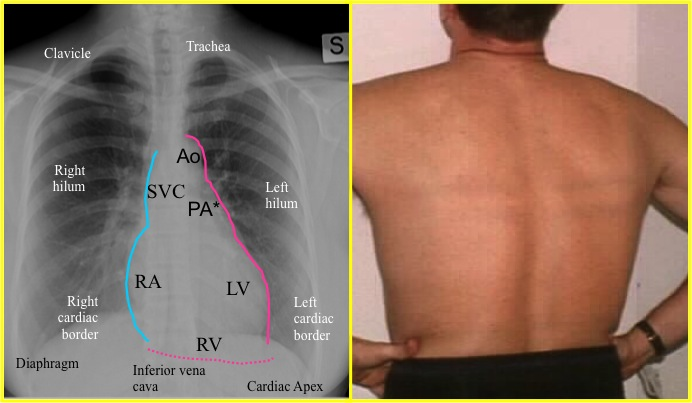

What vessel can be viewed on the anterior side of the heart

LAD

In a lateral chest x ray the coronary sinus is orientated _____ and located near the ______ aspect of the heart

orientated horizontally

near the posterior inferior aspect of the heart

Which structure forms the patents right cardiac border?

what structure normally appears as a circle on the superior aspet of the cardiac silhouette in the AP chest radiograph

Transverse aortic arch or the aortic knob

When viewing the heart in LAO projection what structures form the right cardiac border

Right atrium and right ventricle.